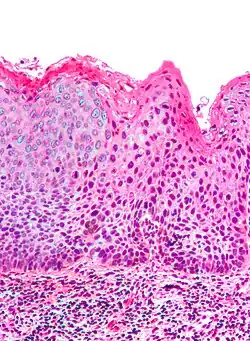

| Micrograph of (classic) vulvar intraepithelial neoplasia III. H&E stain. | |

Micrograph of vulvar intraepithelial neoplasia III. H&E stain. -

Medically speaking, the term denotes a squamous intraepithelial lesion of the vulva that shows dysplasia with varying degrees of atypia. The epithelial basement membrane is intact and the lesion is thus not invasive but has invasive potential.

Classic vulvar intraepithelial neoplasia: associated with developing into the warty and basaloid type carcinoma. This is associated with carcinogenic genotypes of HPV and/or HPV persistence factors such as cigarette smoking or immunocompromised states.